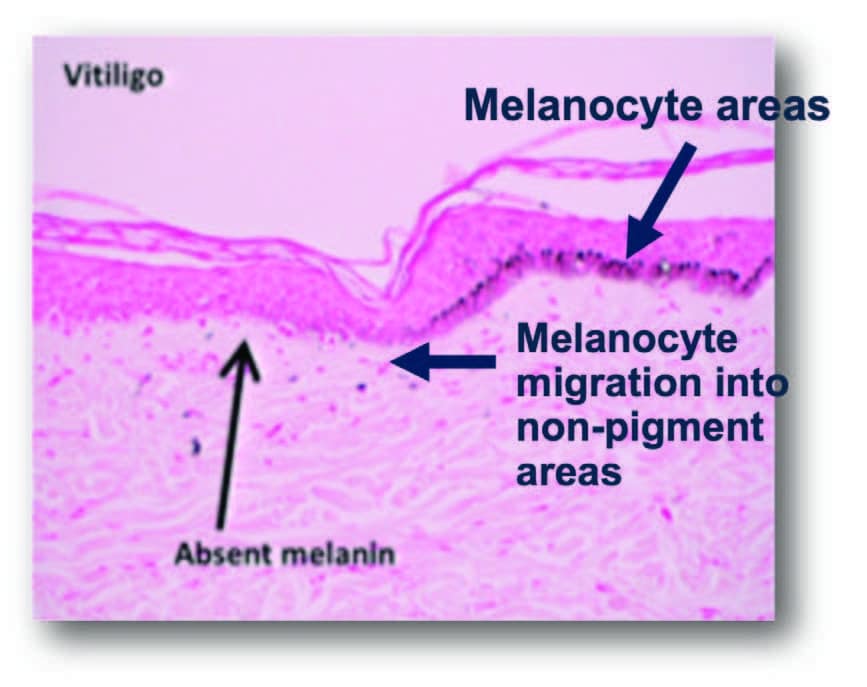

Mechanism of Action:

- Induce the activation, migration, and/or proliferation of melanocytes into hypopigmented areas at the dermal-epidermal(DEJ). This shallow dermis area is the target depth.

- Also, mechanical trauma stimulates the melanocytes migration from the pigmented areas to unpigmented areas.

- Microneedling may increase the number of pigment cells and stimulate more pigment production

- Studies in literature indicate that 6 or more treatments may be necessary to begin to see improvement

Microchannels provide space for melanocytes to migrate into non-pigment areas